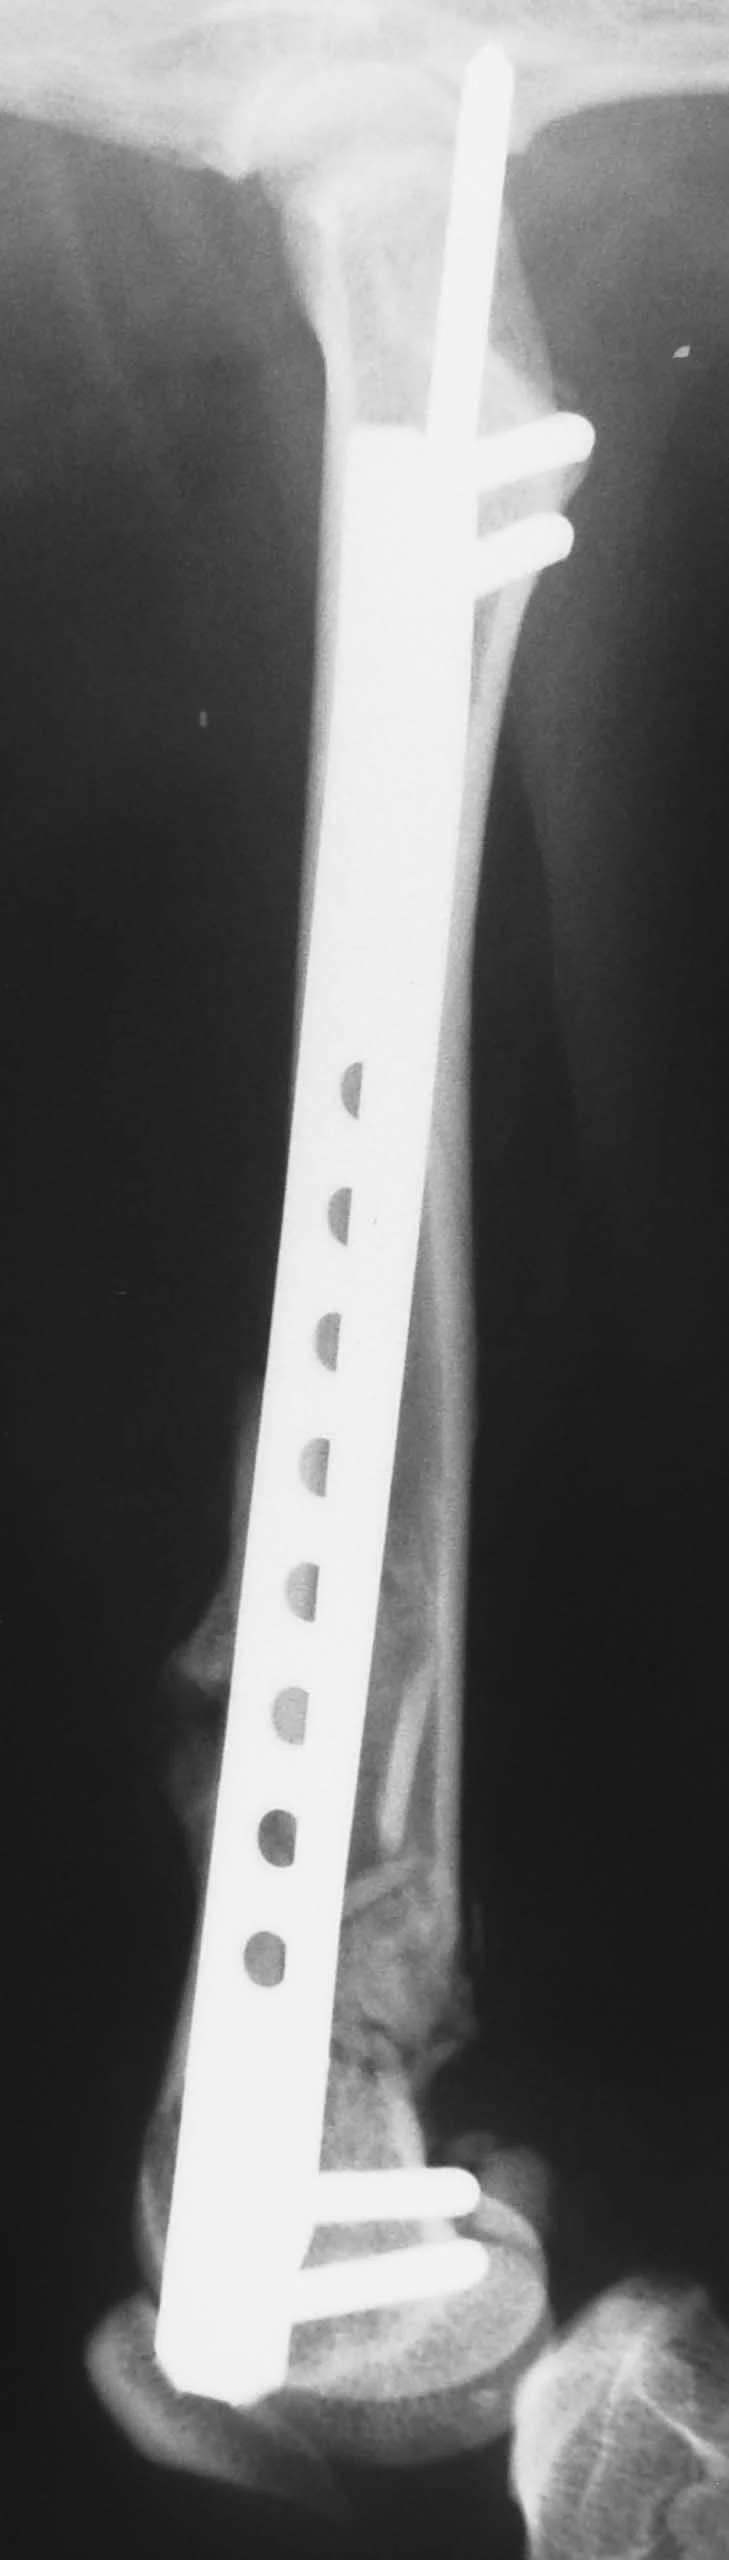

The combination of an IM pin and a bone plate has been found to be an ideal implant system for biologic management of comminuted fractures (Figure 1A) in dogs7 and cats. Adding an IM pin to the plate (Figures 1B, C) significantly increases stiffness and the estimated number of cycles to fatigue failure when compared with a plate-only system.

Adding an IM pin to a bone plate has been shown to reduce strain on the plate two-fold and subsequently increase the fatigue life of the plate-rod system 10-fold compared with the plate alone.2 In the canine femur, plate strain is reduced by approximately 19%, 44%, and 61% with the addition of an IM pin occupying 30%, 40%, and 50% of the marrow cavity, respectively.3

The IM pin is applied first. It can be used to assist distraction of the fracture as it engages the distal fragment. The pin provides axial alignment and provides partial stability for application of the plate.

The surgeon must be careful to attain rotational alignment before placing the screws of the bone plate. Only two to three screws are needed in the proximal and distal fragment. Monocortical screws are placed if the screw cannot be directed to avoid the IM pin. Open screw holes are protected by the IM pin and early bone callus, decreasing the chance of plate breakage.